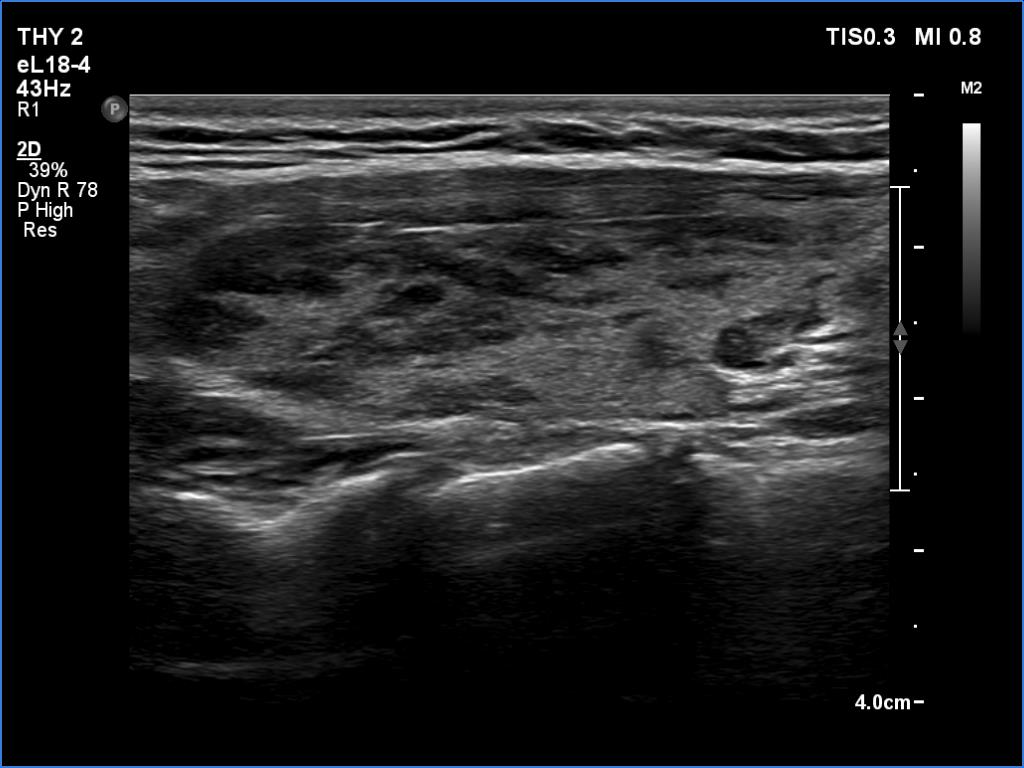

Lymphocytic thyroiditis - case 1441

Right lobe

Left lobe

Focal form of lymphocytic thyroiditis is presented. The thyroid has numerous discrete, hypoechoic lesions which correspond to more active foci of thyroiditis. The interpretation of the relatively large ventral hypoechoic area in the left lobe (right upper image can cause problem), however, longitudinal scan decides the issue: this field cannot be a pathological nodule.